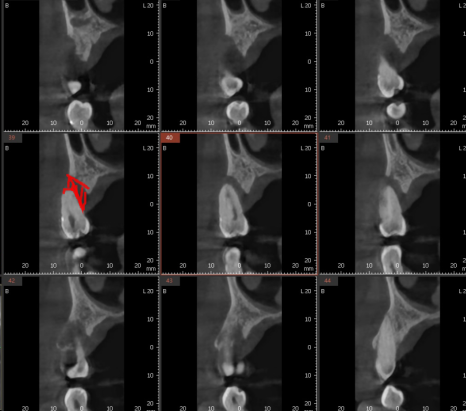

CT 상에서도 뼈가 녹아 치아가 붕~ 떠있는 것을 볼 수 있고요

이럴 때는 발치 후 염증을 깨끗하게 제거

제 2의 치아인 임플란트 식립을 해줍니다.

240712

상일동역 치과에서 임플란트 식립한 사진입니다.

기능을 상실한 치아를 대신하여

임플란트를 심어드렸는데

임플란트 역시 잇몸 뼈에 식립하기에

관리를 해주어야합니다.